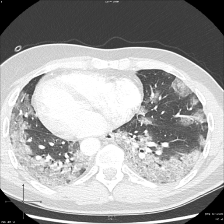

On the other hand, the visualized masks of the comparison methods for the binary and multi-classes Covid-19 infection segmentation are: Unet++ Zhou et al. (2018), CopleNet Wang et al. (2020), MISSFormer Huang et al. (2022) and UCTransUnet Wang et al. (2022a), and for multi-classes segmentation task are Att-Unet Oktay et al. (2018), SCOATNet Zhao et al. (2021), MISSFormer Huang et al. (2022) and UCTransUnet Wang et al. (2022a), which showed a competitive performance with our proposed approach (see Section 5.4).

Figure 7 consists of the visualization of three examples masks using our approach and the comparison architectures for multi-classes Covid-19 segmentation. The first example shows a mixture case of GGO and Consolidation, where most of the infected regions consist of consolidation and small GGO regions are attached to the consolidation regions. Unlike the masks of the comparison architectures, the mask of our approach has a high similarity to the ground truth mask for both the consolidation and GGO classes. The second and third examples also represent a case where both GGO and consolidation are present in both lungs. The infected regions with consolidation are mainly in the lower lobes of both lungs and GGO spreads in both lungs with peripheral and posterior distribution. The masks of these examples confirm the observation in the first example, as the predicted masks of D-TrAttUnet show a high similarity to the GT masks for both infection types GGO and Consolidation.

Refer to caption Refer to caption Refer to caption Refer to caption Refer to caption Refer to caption Refer to caption

Slice AttUnet SCOATNet MISSFormer UCTransNet D-TrAttUnet GT

Figure 7: Visual comparison of a segmentation model trained with different segmentation architectures for Multi-classes (No-infection, GGO and Consolidation) Covid-19 infection segmentation using Dataset_2. GGO is presented by the Green color and Consolidation by the red color.